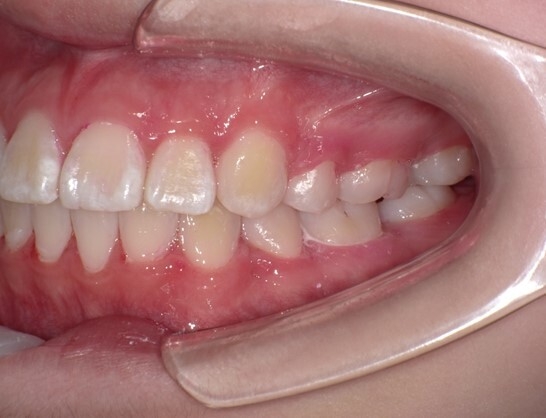

患者は13歳8か月の女子。主訴は左上に八重歯があること。上顎両側、下顎左側第一小臼歯を同時抜歯し、JET systemで治療を行ったところ動的治療期間は7か月であった。前歯部のトルクコントロール、上下顎正中の一致、咬合関係の改善が行われた。抜歯により誘発されたRAPを利用したJET systemでの治療は、治療期間の短縮に寄与し、患者QOLを向上させることが示唆された。

この症例のように身体の成長途上にある中高生であれば、治療を6~9か月で終えることができる可能性があります。歯列矯正治療では、平均して治療に2~3年にわたることが一般的ですが、JET systemによる最も顕著な患者さんのメリットは治療期間の短縮です。長期にわたる治療のストレスや生活の制約、ブラケットによる見た目への懸念、矯正装置の使用にともなう不快感を短期間で終えることができます。また、JET system専用に開発したブラケットを使用することで、これまでよりも弱い矯正力で治療を行うため痛みが少なくなります。JET systemは、患者さんのモチベーションを維持し、治療効果や患者さんの満足度向上につなげることが期待できます。